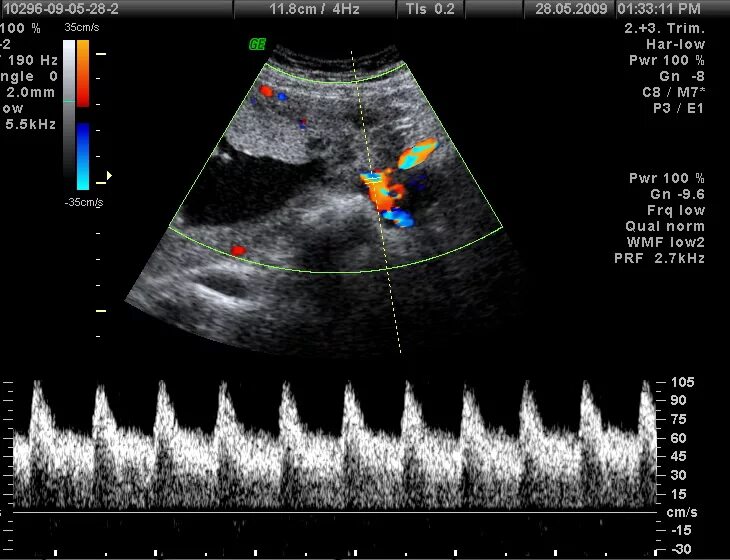

Допплер для беременных для чего